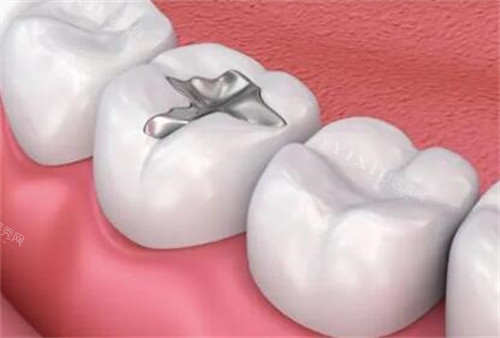

3. 仿生牙修复技术

爱顿口腔的仿生牙技术通过精密设计和高质量材料应用,使修复体稳定牢固、美观舒适。这种技术不损伤邻牙,能够提供强大的咀嚼力,外观与真牙几乎无异,为患者带来自然的使用体验。